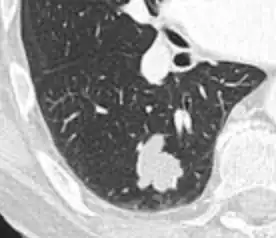

-

Part solid nodule.[9] -

Ground glass opacity nodule.[9]